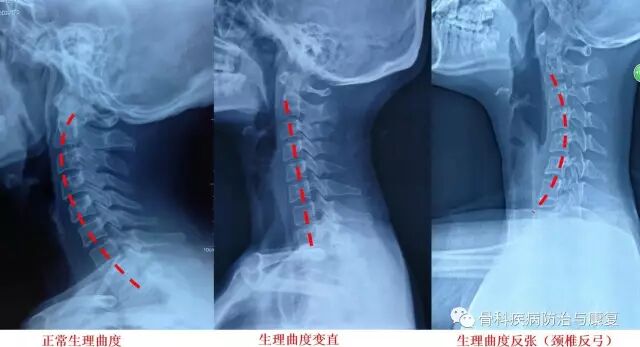

颈椎反弓的正侧位X片

颈椎反弓是一种常见颈椎病。正常颈椎呈现“C”形向前的生理弧线,它既保证了颈椎活动的高度灵活性,又减轻了颈椎间盘的重力负荷,使颈椎处于最佳的力线状态下工作。如果没有生理弯曲,颈椎会出现僵直,甚至向相反的方向弯曲,就称为颈椎反弓。

颈椎生理曲度不同改变X片表现?